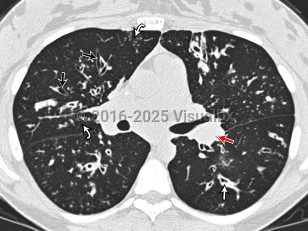

Cystic fibrosis in Infant/Neonate

Only about 4% of cystic fibrosis patients are diagnosed as adults. Adult patients may also develop pancreatic endocrine insufficiency and cystic fibrosis-related diabetes, which involves both insulin deficiency and resistance. Most adult cystic fibrosis patients will ultimately die of respiratory failure.

Pseudomonas aeruginosa, Staphylococcus aureus, and Mycobacterium abscessus infections are complications of cystic fibrosis. Patients with cystic fibrosis may be anemic. Patients often have impaired absorption in the small bowel and ciliary dysfunction in the genitourinary system that can impact fertility.